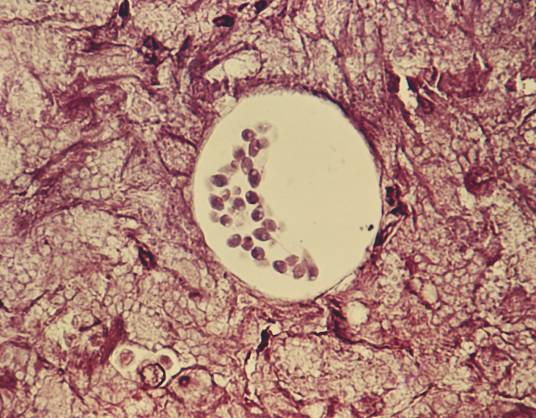

孢子虫卵囊呈圆形或椭圆形,孢子虫成熟卵囊内含4个裸露的子孢子和残留体孢子虫残留体由颗粒状物。孢子虫在改良抗酸染色标本中,孢子虫卵子孢子排列不规则,孢子虫形态多样隐孢子虫完成整个生活史只需一个宿主。